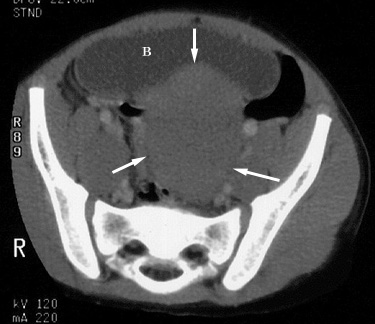

Understanding CT Scan Results - About.com Health

Understanding CT Scan Results 2. Indications and Risks of a CT Scan versus an MR… 3. Understanding MRI Results 4. Intracerebral Hemorrhage: A Rare but Dangerous… 5. A Research Success for Endovascular Stroke Trea… About.com; About Health; ... Read Article